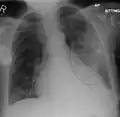

Left upper lobe pneumonia with a small pleural effusion.

Right lower lobe pneumonia as seen on a lateral CXR